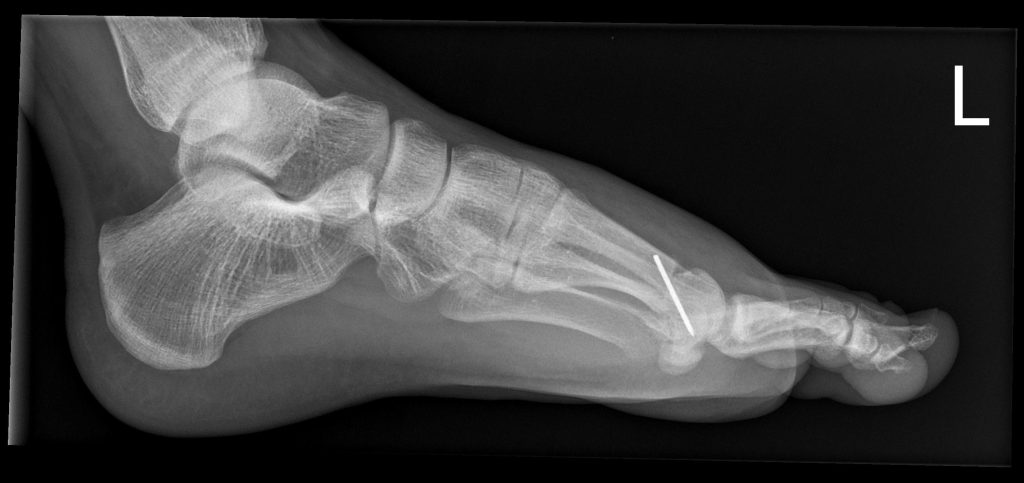

- Röntgen zur Beurteilung von Gelenkspalt, Osteophyten, Stellung

Youngswick Osteotomie

(Arthrose Gelenkspalt mehr als 50%, langer erster Mittelfußknochen)

Ist eine Modifikation der Chevron-Osteotomie ( OP bei Hallux valgus) dabei wird eine V- Förmige gelenknahe Durchtrennung des ersten Mittelfußknochens durchgeführt . ( in Kombination mit einer Cheilotomie) und eine Knochenscheibe entnommen, dadurch kommt es zu einer Verkürzung des ersten Strahls und einer Druckentlastung des Gelenks, was einer Verbesseerung der Beweglichkeit und Reduzierung der Schmerzen führt. Diese Operation führen wir häufig bei noch erhalten Gelenkspalt als Alternative zur Versteifung durch.